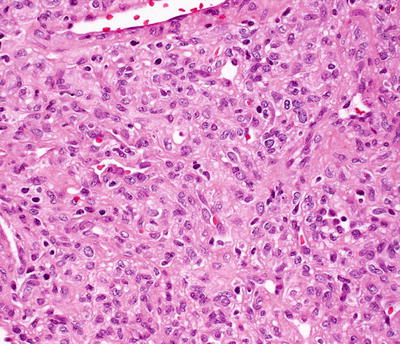

Infantile hemangiomas are densely cellular endothelial cell tumors that occupy the entire dermis, and may extend into the underlying subcutis [146]. Small blood vessels are present with a dense cellularity that includes endothelial cells, pericytes, and stromal fibroblasts [147] (Figs. 21.15, 21.16 and 21.17). Abundant mitoses are present, but there is minimal cytologic atypia. Frequent apoptotic endothelial cells are seen [148]. Many lesions demonstrate extensive areas of dense cellularity with relatively insignificant vascularity; however, on close inspection, areas of vascular proliferation can be detected focally (Fig. 21.18). An infiltrative growth pattern with extension of the hypercellular areas into surrounding collagen and subcutaneous fat causes these lesions to resemble malignant neoplasms [147]. As the lesions progress, the cellularity diminishes, blood vessels become more dilated and lobular in their configuration.

Fig. 21.15

Infantile hemangioma demonstrates densely cellular lobules of small, well-formed blood vessels in the dermis

Fig. 21.16

Well-formed blood vessels and a dense proliferation of ovoid cells are present in infantile hemangioma . The relative amounts of vascularity and surrounding cellularity vary with the age of the lesion

Fig. 21.17

A dense proliferation of blood vessels lined by benign endothelial cells and surrounded by pericytes and stromal cells characterizes the appearance of an infantile hemangioma

Fig. 21.18

A hypercellular proliferation of epithelioid and spindle-shaped cells is present in infantile hemangioma